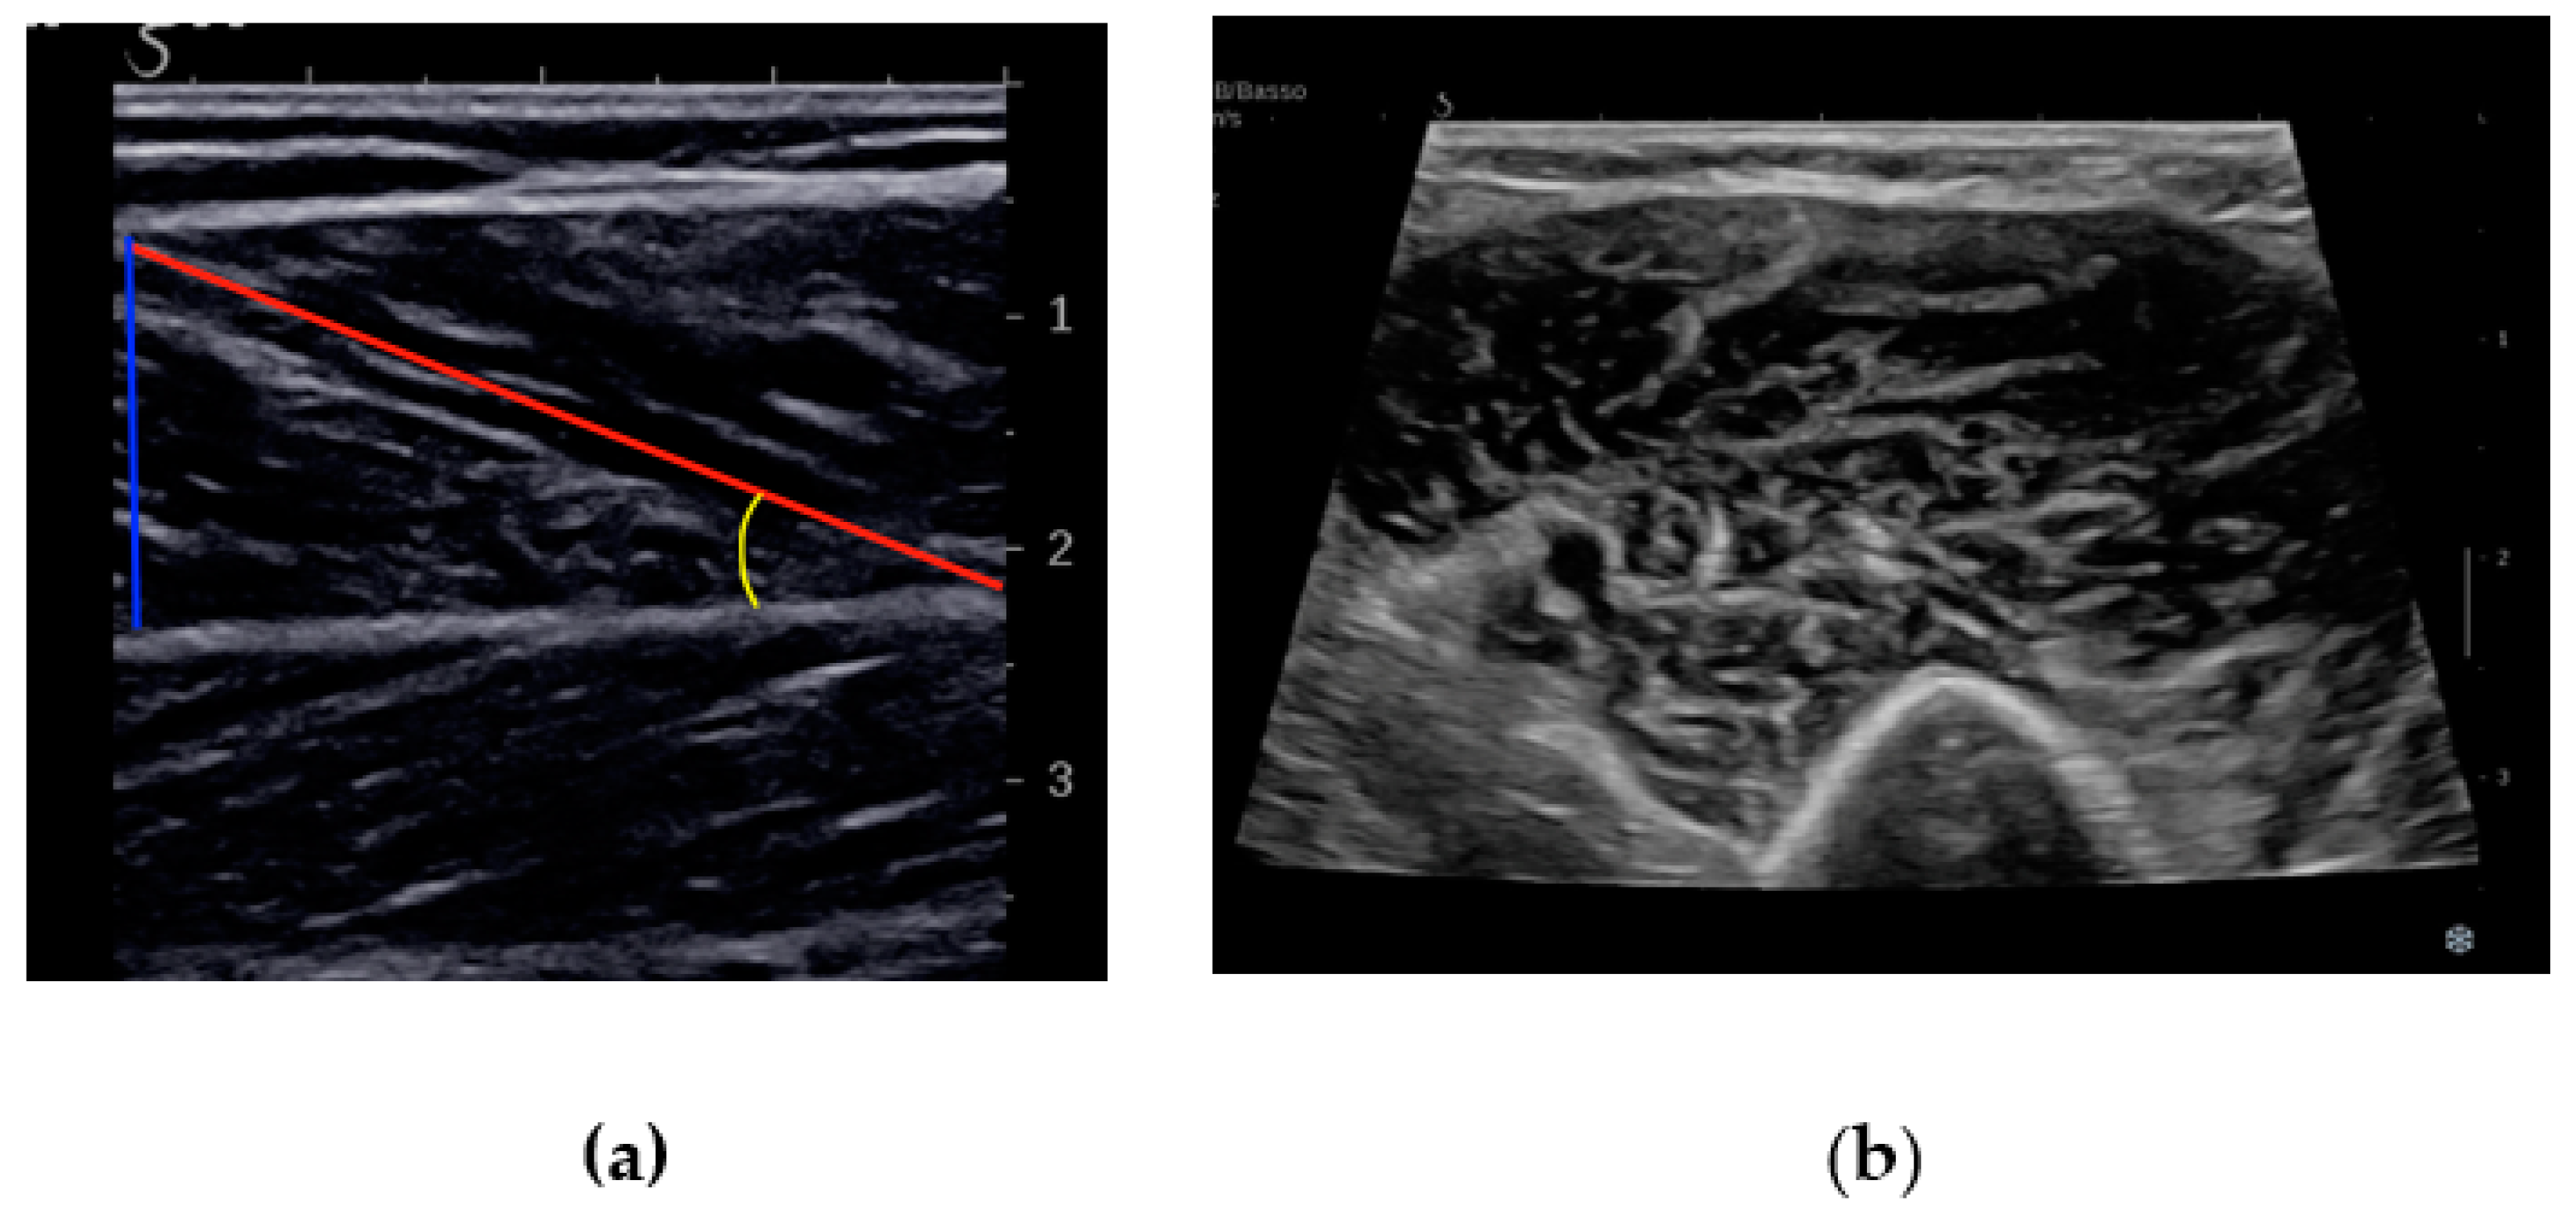

- Kawakami, Y.; Abe, T.; Fukunaga, T. Muscle-fiber pennation angles are greater in hypertrophied than in normal muscles. J. Appl. Physiol. 1993, 74, 2740–2744. [Google Scholar] [CrossRef]

- Randhawa, A.; Wakeling, J.M. Associations between muscle structure and contractile performance in seniors. Clin. Biomech. 2013, 28, 705–711. [Google Scholar] [CrossRef]